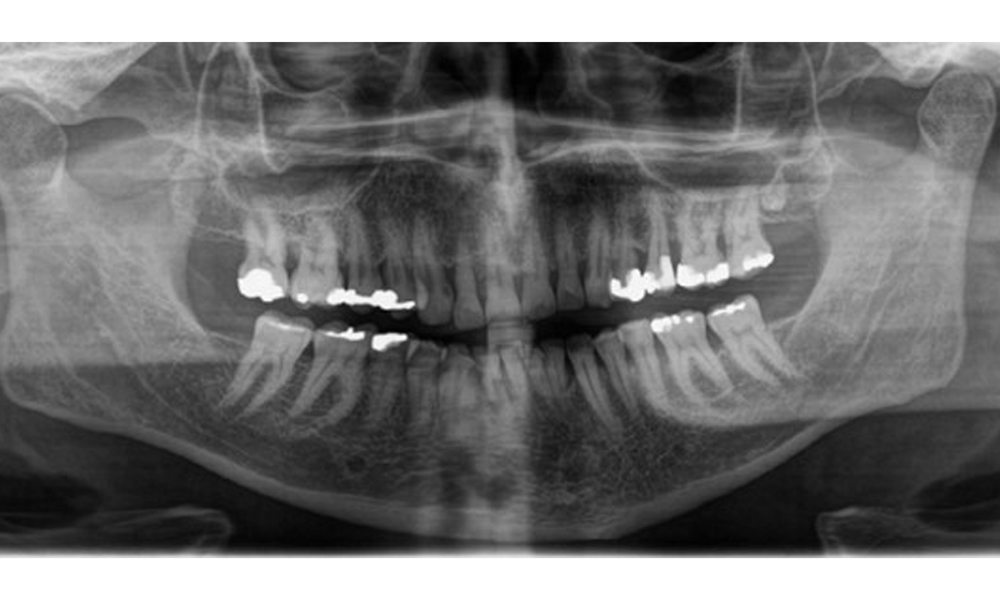

Radiologischer Befund

Es zeigt sich ein vollbezahntes Erwachsenengebiss mit einem generalisiertem Knochenabbau zwischen 20-50% und multiplen vertikalen Knocheneinbrüchen. Radiologisch ist keine kariöse Läsion sichtbar. (Abb. 7)